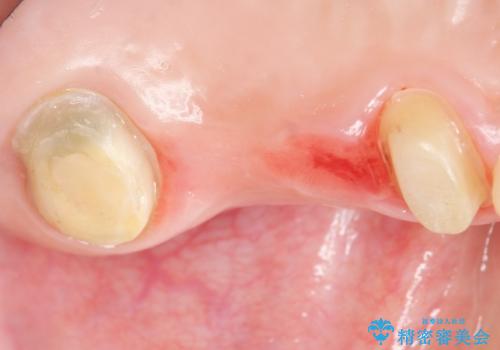

- う蝕により奥歯がボロボロになってしまい、咬むことができないことを主訴に来院された患者様です。

奥歯3本(左上567)はう蝕が深く保存不可能な状態であったため、やむなく抜歯しました。

インプラントも入れ歯も抵抗があるとのご相談により、自家歯牙移植を提案しました。

使っていない親知らず(左上8)を左上7抜歯窩に移植し、支台歯としてブリッジによる補綴治療を行いました。